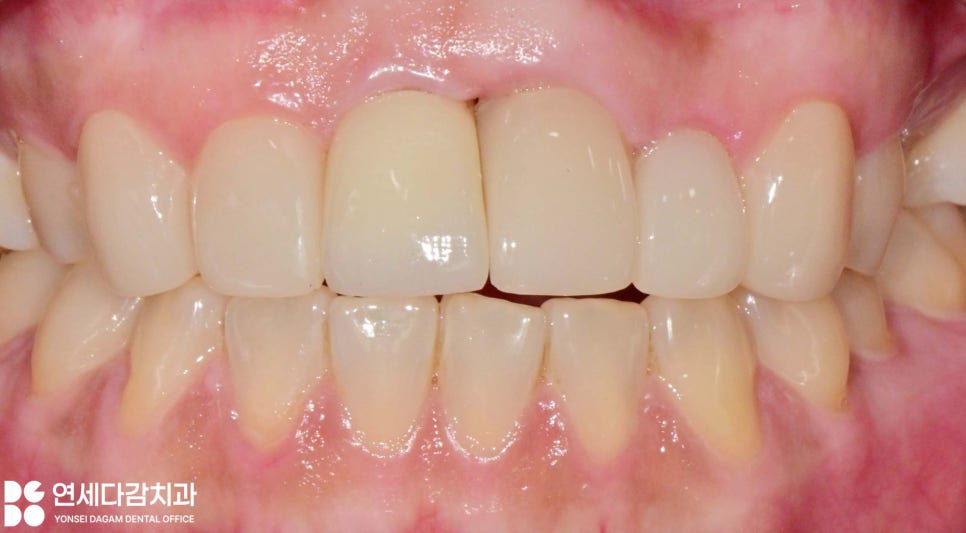

라미네이트와 크라운을 재제작할 때는

돌출된 치아의 모습을 개선하기 위한

구조로 계획했기에,

기존 임플란트 크라운은 돌출도를

감소시킬 수 있는 형태로 재제작하고,

인접해 있는 자연치들은

최소한으로 다듬어 조화로운

형태가 만들어질 수 있도록 합니다.

이전보다 잇몸과 치아의 심미가

확연히 발전된 것을 확인할 수 있습니다.

치료 전에는 웃을 때

아래 앞니만 보이게 웃는

모습이었으나,

치료 이후로는 위 앞니가 보이게

환하게 웃는 모습을 보이게 됩니다.

이러한 변화는 자신감과

삶의 질을 개선하는 의미 있는 변화입니다.